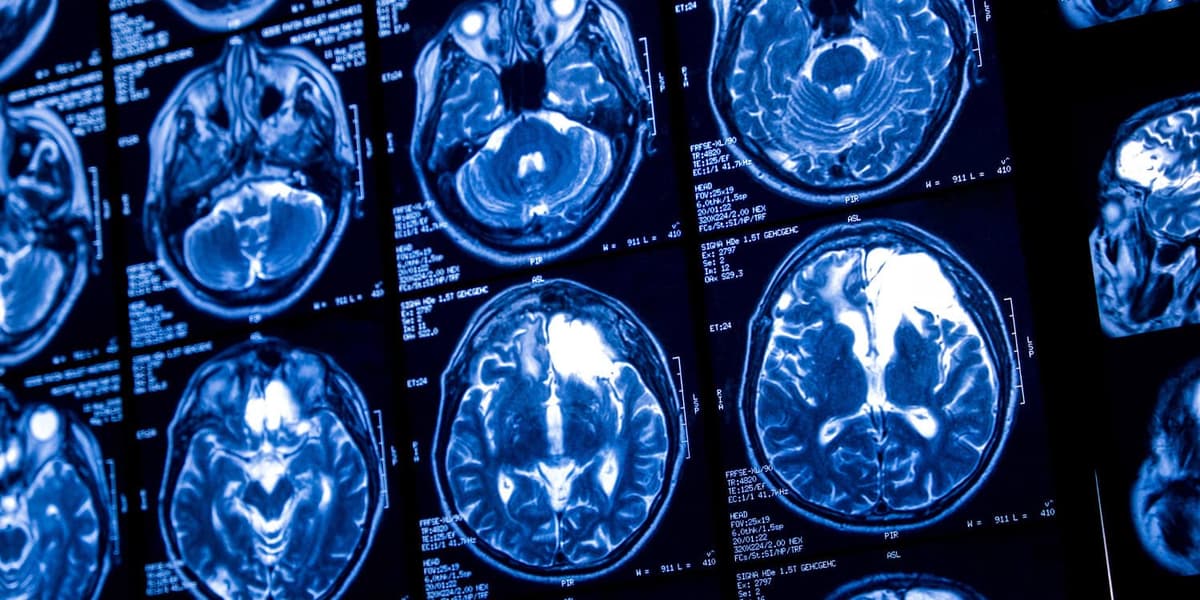

Even Light Drinking Combined with Aging Is Linked to Reduced Brain Blood Flow and Thinner Tissue

A Stanford‑led study published in *Alcohol* found that even low‑level alcohol consumption, when combined with aging, is associated with reduced cerebral blood flow and thinner cortical tissue. Researchers examined 45 healthy adults (22‑70 years) and measured lifetime drinking patterns, brain...